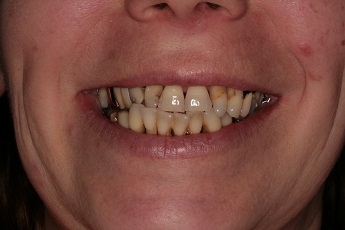

3) fotodokumentace - fotografie stavu chrupu a otisky na studijní modely

Fotodokumentace a model se provádí u pacientů s potřebou kompletní rekonstrukce chrupu.

Foto 9-13: Fotodokumentace situace v ústech - vlevo, vpravo, uprostřed, v horní a dolní čelisti.

Foto 14, 15: Vlevo zuby v úsměvu před ošetřením chrupu. Vpravo fotografie skusu zubů.